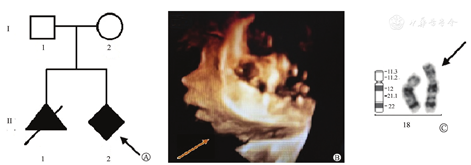

A: 家系图, 箭头示先证者; B: 胎儿超声三维轮廓, 箭头指示处提示胎儿下颌稍后缩; C: 胎儿羊水18号染色体核型及模式图, 箭头示衍生的18号染色体

孕12+1周超声检测, 单胎, 相当于12+4周, 颈项透明层(nuchal translucency, NT) 1.7 mm, 顶臀径64 mm, 羊水深度33 mm, 表现无异常。孕22周胎儿大结构畸形筛查, 依据早孕期超声, 核实了孕周, 胎儿估重与纠正后孕周相符, 依据二级超声影像标准, 该胎儿未检测出显著大结构发育异常, 二维轮廓未见明显异常, 三维轮廓提示胎儿下颌稍后缩(图1B)。

胎儿羊水染色体核型分析结果为46,XY,der(18)(图1C), 胎儿母亲和父亲外周血染色体核型分析结果分别为46,XX和46,XY。

患者23+4周选择性引产终止妊娠。娩出胎儿身长30 cm, 顶臀径20 cm, 头围20 cm, 双顶径6.5 cm, 胸围16 cm, 腹围15 cm, 耳位低, 三角脸型, 颧骨发育不良, 下颌后缩, 外生殖器男性, 阴茎阴囊正常, 四肢脊柱无异常。